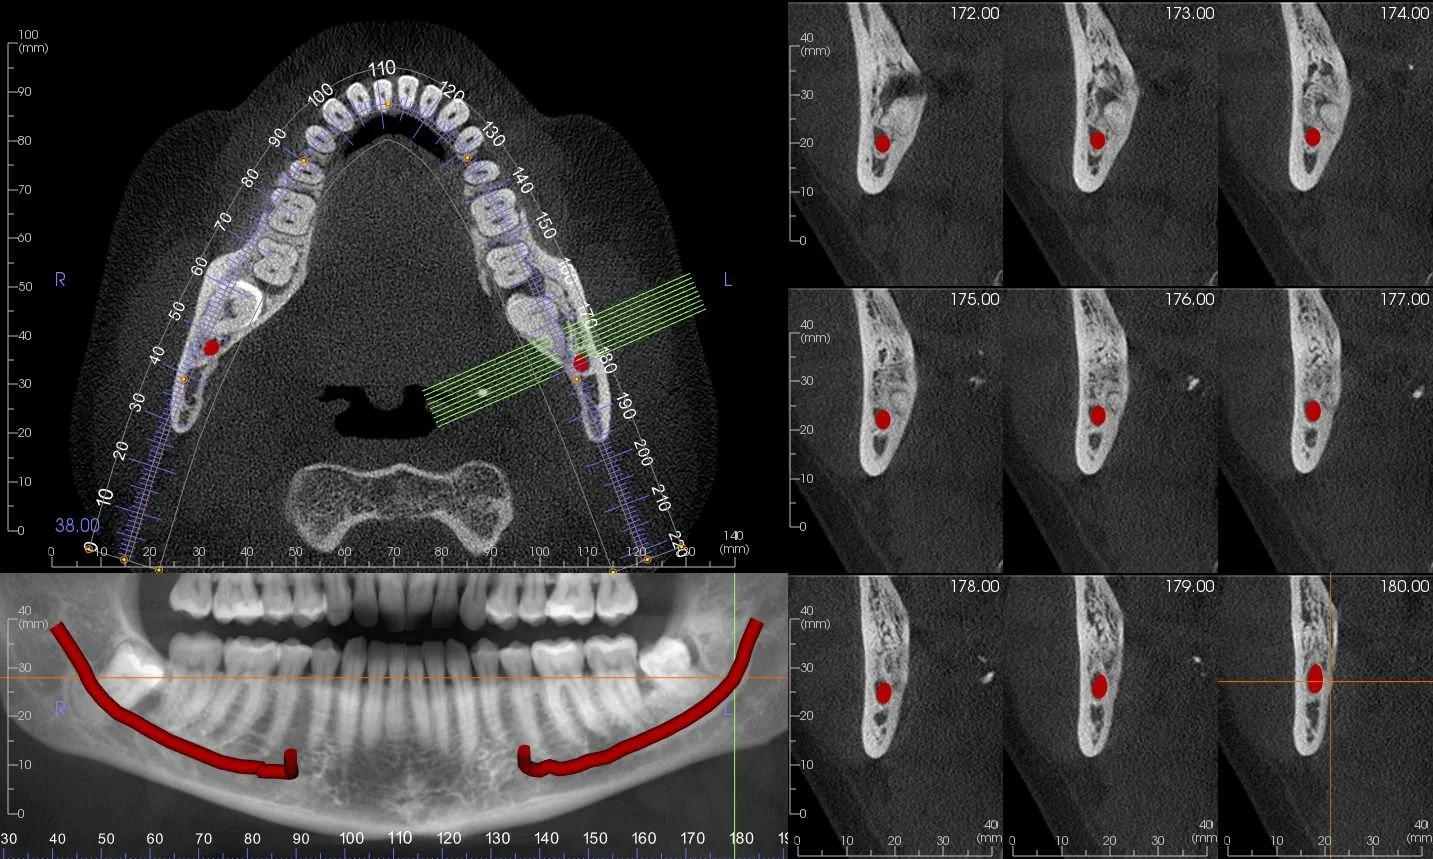

Visualization of virtual dental Implant Placement  in  Cone Beam CT image

Nerve canal tracing on Cone Beam CT Image

• Our surgical guides are custom, patient specific devices designed and created from 3D imaging data to assist implant placement during dental implant surgery. The purpose is to guide the precise placement of dental implants within the patient’s jawbone with optimal accuracy thereby minimizing the risk of any errors or misplacement.

• Orbit's Implant Plans are created in 3 Shape Implant Studio planning environment. by an experienced dental professional in collaboration with the implant dentist or specialist. The plans are prosthetically driven and include an interactive planning session with the referring clinician. The resulting plan can be used to create a surgical guide by Orbit or or by a preferred dental laboratory.